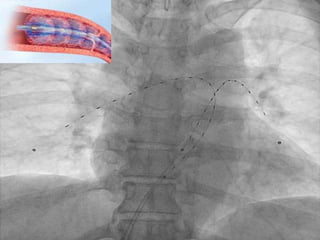

• Prospective, RandomizedControl Trial • SUBMASSIVE PTE ONLY!!! • 59 patients • Primary Outcome – Difference of RV/LV at 24o • Safety Outcome – Death, bleeding, and recurrent VTE at 90-days Kucher N. Circulation. 2014;129:479-486

• 54.

• Results – PrimaryEnd Point • USAT = RV/LV reduced by mean 0.29 • Heparin = RV/LV reduced by mean 0.03 – Safety End point • No episodes of hemodynamic decompensation or recurrent VTE in either group • Bleeding – USAT = 3 minor bleeding complications – Heparin = 1 minor bleeding complication Kennedy RJ. J Vasc Interv Radiol. 2013;24:841-848

• #51 Catheter inserted in affected throbus and left in place for a period of time (15hr). US is then delivered to to promote dissociation of the fibrin matrix and increase penetration of locally delivered fibrinolytic

• #54 Ultrasound Accelerated Thrombolysis of Pulmonary Embolism Randomized to US assistaed thrombolysis + heparin or heparin alone Placement of US catheter into clot with local fibrinolytics for 15hr RV/LV ratio measured via ECHO

• #55 At 90-days though the RV/LV difference between groups was only 0.04 USAT Bleeding – 2 transient episodes of hemoptysis and 1 groin hematoma Heparin Bleeding – 1 muscular hematoma and anal bleeding after endoscopic colonic polyp removal at 80-day

• #56 Often thought of as last resort Retrospective review of 47 patients who underwent surgical embolectomy Indications – Contraindications for thrombolysis, failed therapy (thrombolytics/catheter), RV dysfunction, large RV/RA thrombus Improvement due to advances in surgical technique, anesthesia, and more aggressive initial identificaiton and maagement